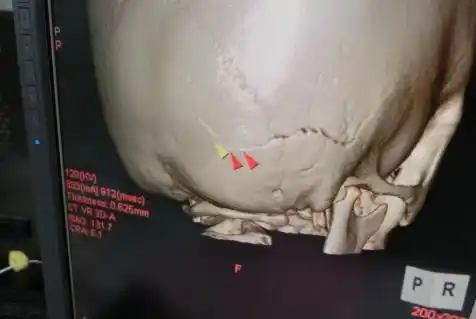

走り回ってる子供の頭蓋骨骨折、

「元気に廊下を走り回っている幼児でも頭蓋骨骨折あり」